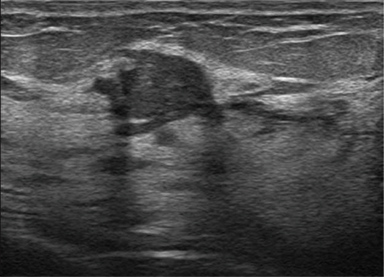

OFF

ON